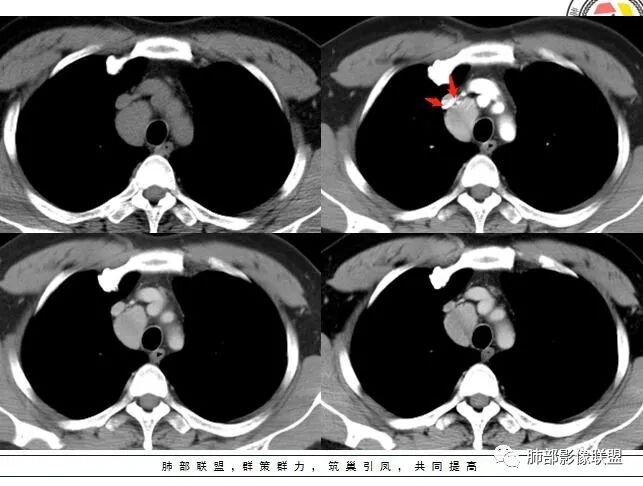

男,40岁,体检发现纵隔占位

•查血常规、血生化、肿瘤标志物、尿常规大致正常。气管腔静脉间隙团块状影,密度均匀,边界清楚,增强扫描,明显的强化,肿块的周围气管旁见多个肿大的淋巴结,强化特点类似。考虑良性占位,巨淋巴增生症。需要与异位胸腺瘤、结节病、淋巴瘤、副神经节瘤、淋巴结转移瘤鉴别。

病灶位于上腔静脉内侧,定位没有疑问,来自纵隔。上腔静脉内侧有什么,有淋巴。膈神经在外侧。迷走神经在后侧

中年男性右上纵隔椭圆形软组织肿块,边界清,密度均匀,明显均匀强化(峰值在动脉期),周围见小血管影进入及有小淋巴结,考虑CD>副节。

右前中纵隔软组织肿块,有钻缝生长特点,边界清,周围脂肪血管未见受侵,增强动脉期明显强化,明显持续强化,内部及周围见血管,周围见小淋巴结,考虑CD,鉴别淋巴瘤,强化不支持;胸腺瘤,不常见部位,形态也不支持;副节瘤,这么大肿块坏死囊变应很明显;神经内分泌肿瘤,强化太均匀、生化不支持,周围结构改变也不符合;神经鞘多有AB区,渐进性强化!

动脉期显著强化,结节呈“门状结构”附近多发子灶——CD!

3.1单发型CD的肺部表现

单发型CD多为透明血管型,所以明显强化和中央分枝状钙化具有特征性。在CT上表现圆形或类圆形软组织密度影,伴或不伴周围淋巴结增生,体积一般较大,边缘光整,病灶中央的弧形、线样、分枝样及枯枝样钙化(因为肿块内增生的血管组织玻璃样变或退变后钙盐沉积,故多呈血管样铸型的分支状或枯枝状);透明血管型因为其内血供丰富,周围可见粗大的供血动脉,在多期扫描动脉早期明显强化,强化程度与大血管相仿,又由于病灶内血管壁玻璃样变或纤维化及内皮细胞过度增生致血管腔狭窄,对比剂退出减慢,故延迟扫描扫描仍可持续强化,呈“早进晚出”的强化方式。因为其血供丰富,坏死、囊变或出血少见,但是有时候病灶内灶状或条片状低密度影,是纤维组织或发生玻璃样变性的血管结构,而不是缺血坏死区。